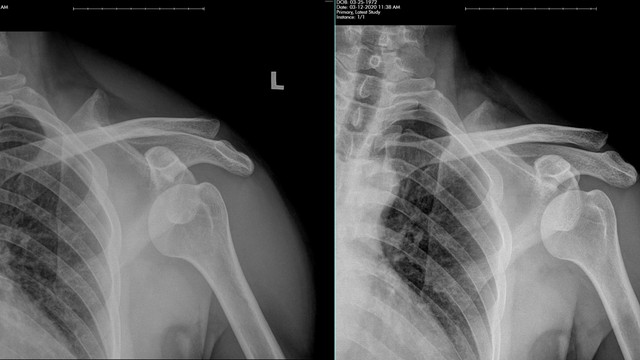

Trật khớp vai là một vấn đề khớp thường gặp, có thể gây ra nhiều khó khăn và bất tiện trong sinh hoạt hàng ngày của người bệnh. Sự không ổn định của khớp vai có thể dẫn đến các triệu chứng đa dạng và trong một số trường hợp, có thể dẫn đến những biến chứng nghiêm trọng. Việc hiểu rõ về các triệu chứng và biến chứng của trật khớp vai là rất quan trọng để có thể đưa ra các phương pháp điều trị phù hợp và phòng ngừa hiệu quả.

Trong cuộc sống hằng ngày, chúng ta thường dễ dàng gặp chấn thương không mong muốn, một trong số đó là các chấn thương trật khớp vai. Hình ảnh trật khớp vai hiện lên trong tâm trí khi nghĩ đến các chấn thương phổ biến, đặc biệt là ở những người tham gia các hoạt động thể thao hoặc lao động nặng nhọc. Việc hiểu rõ về trật khớp vai sẽ giúp chúng ta phòng tránh và xử lý kịp thời những tình huống khẩn cấp này.